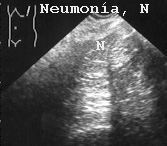

La Fig 50 está producida por una neumonía en un adulto.